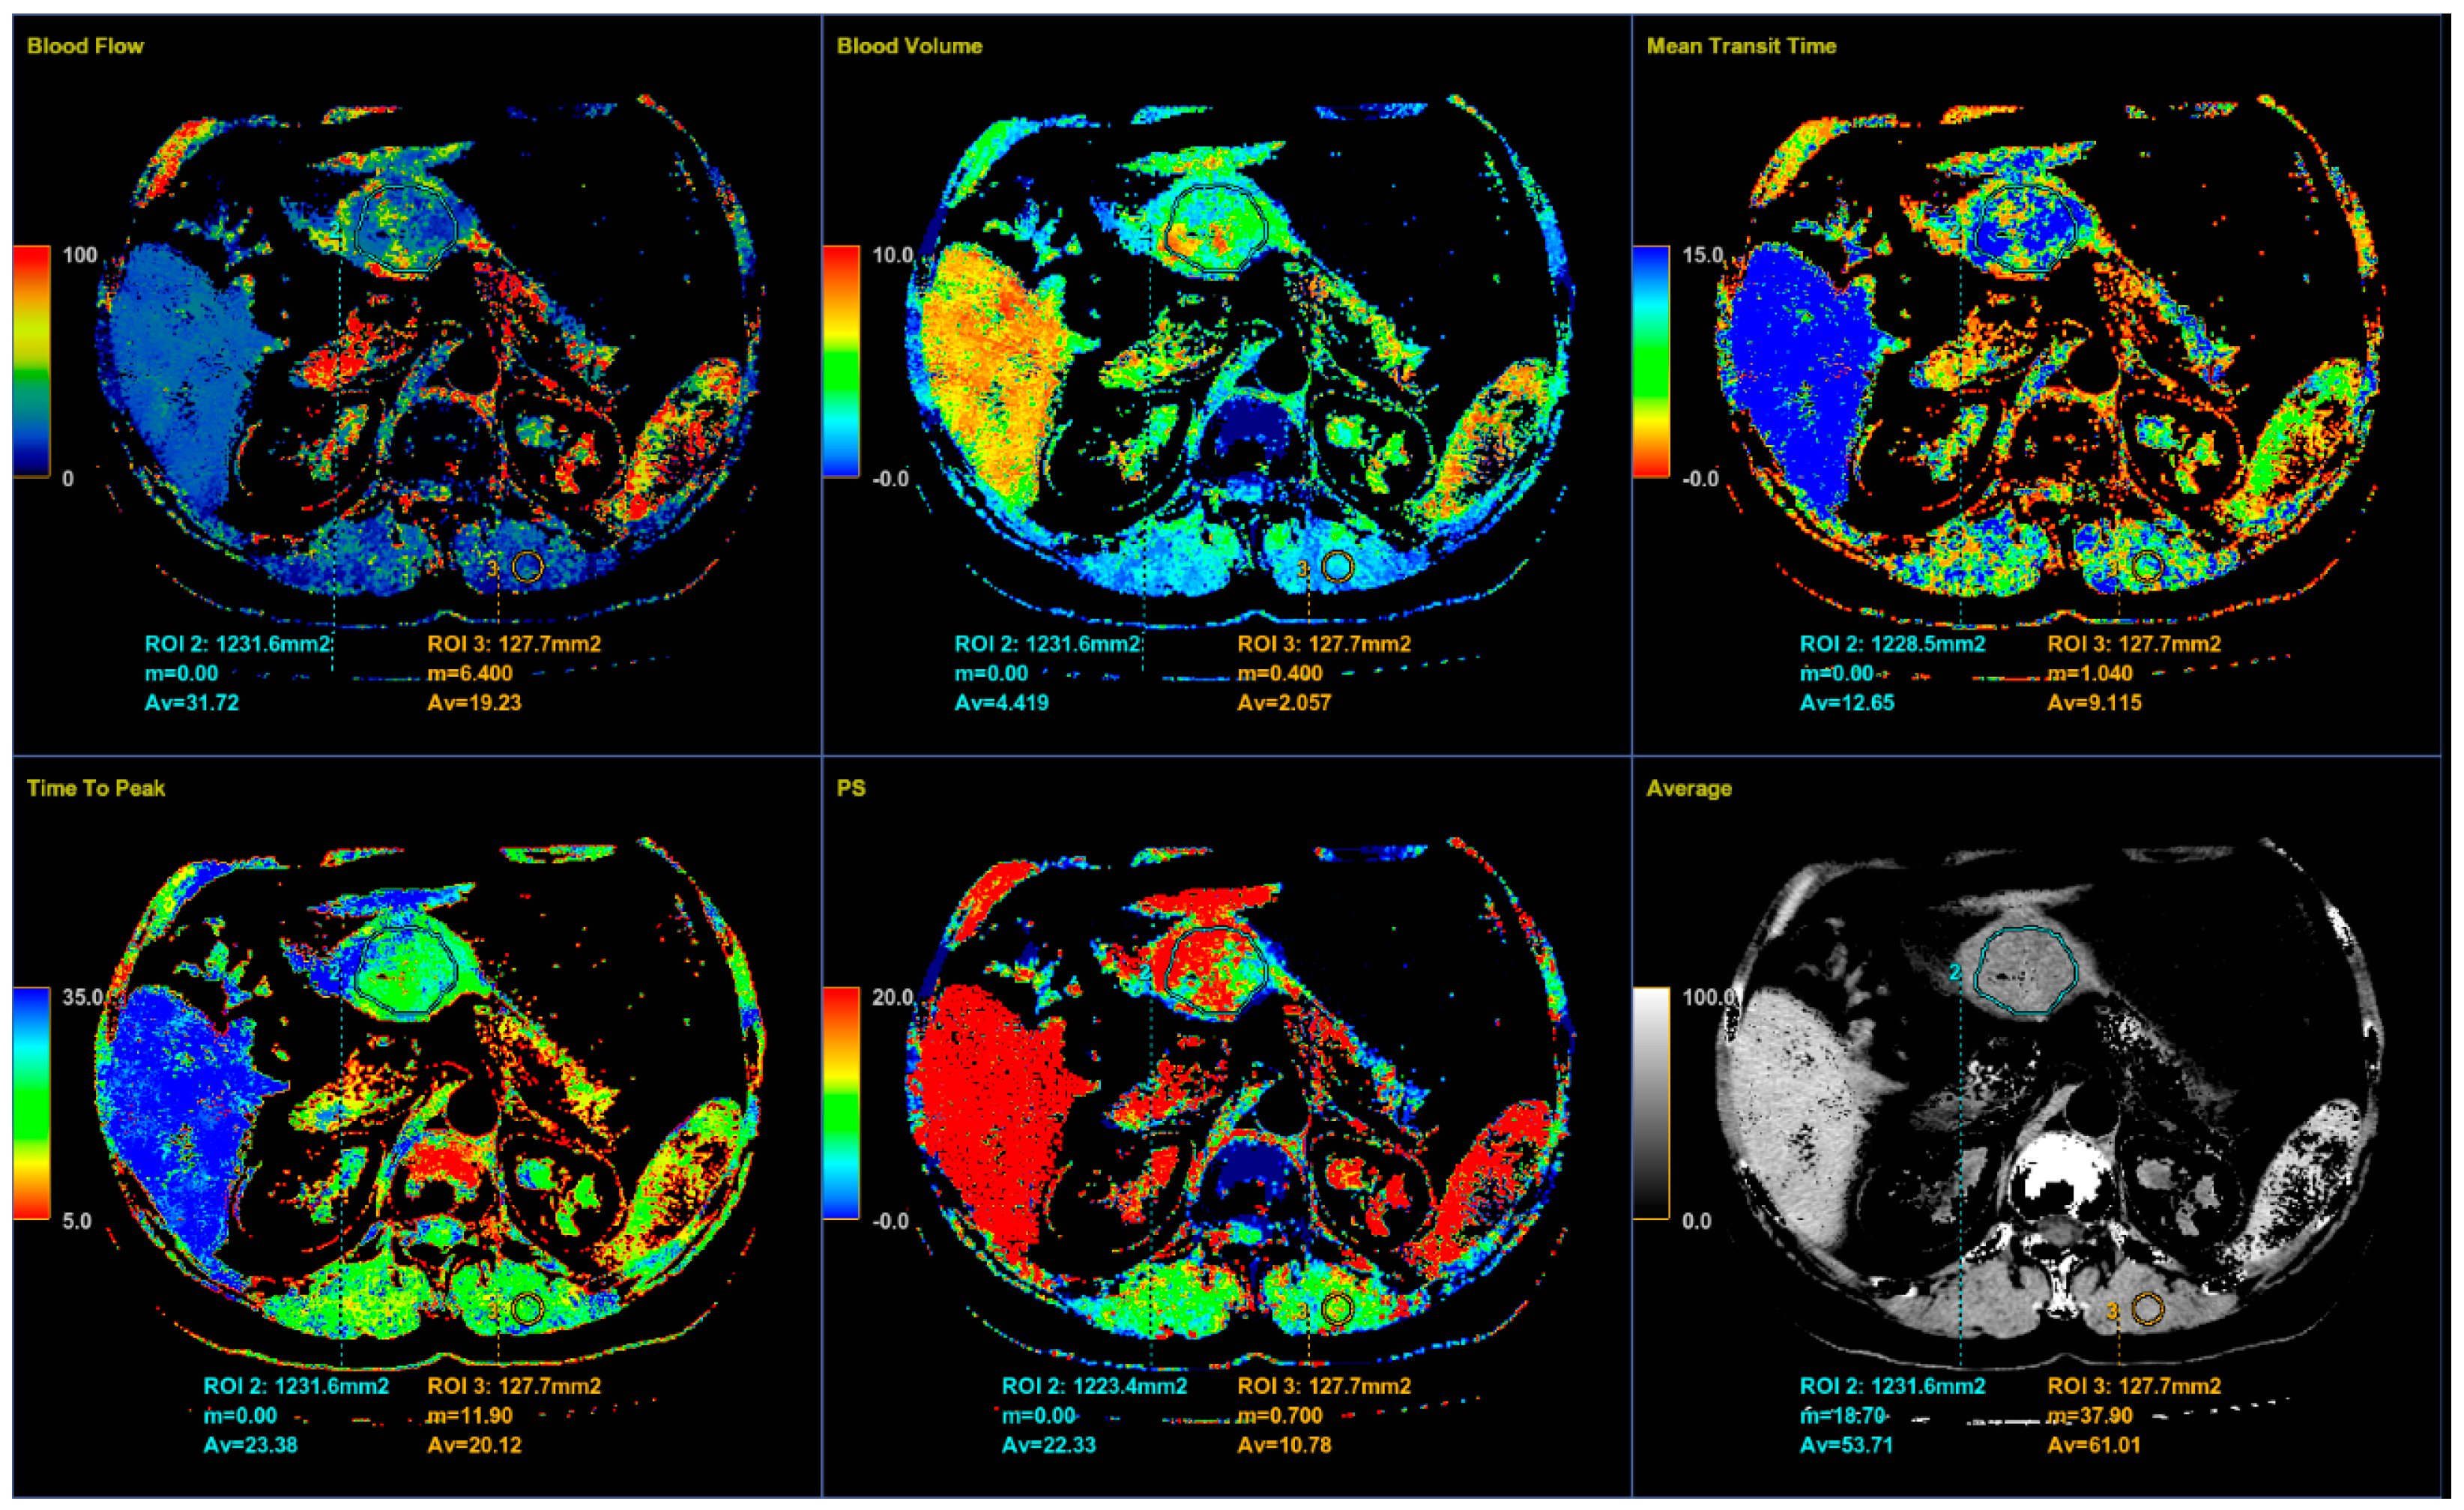

Color parametric maps of the following quantitative perfusion parameters have been automatically computed within these ROIs using the commercial software (Body Perfusion 4.0, GE Health-Care Technologies, USA): blood flow—BF (mL/min/100 g tissue); blood volume—BV (mL/100 g tissue); mean transit time—MTT (s); permeability surface area product—PS (mL/min/100 g tissue); and time to peak—TTP (s) (Figure 5). The values of the perfusion parameters of tumor were recorded for each section of gastric tumor ROI, and the same was done for muscle ROIs. Mean values of the perfusion parameters derived from the four consecutive sections were averaged and used for further analysis.

Figure 5.

Color parametric maps of the same tumor and muscle ROI (area in square millimeters) automatically computed by the commercial deconvolution-based CT perfusion software. Axial CT sections show the average values of perfusion parameters BF, BV, MTT, TTP, PS, and average density measured for tumor and muscle.